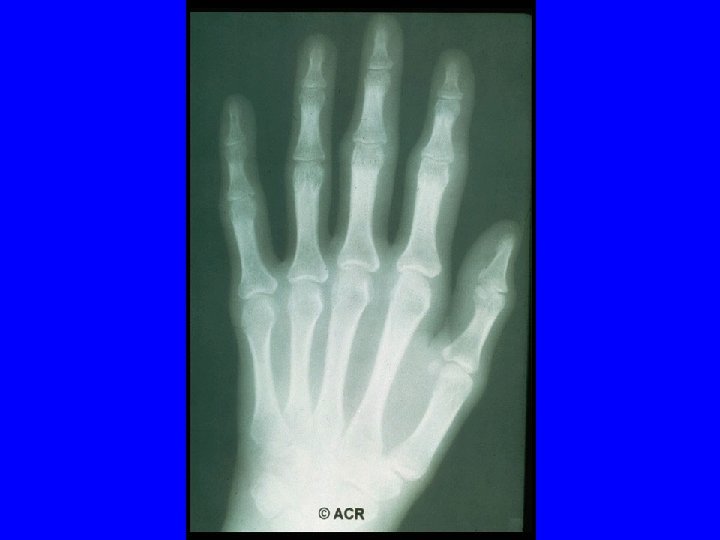

ACR 1987 Classification Criteria For Rheumatoid Arthritis Patients Must have Four of Seven Criteria Morning Stiffness Lasting at Least 1 Hour* Swelling in 3 or More Joints* Swelling in Hand Joints* Symmetric Joint Swelling* Erosions or Decalcification on X-Ray of Hand Rheumatoid Nodules Abnormal Serum Rheumatoid Factor * Must Be Present at Least 6 Weeks

Baseline Evaluation of Patients · Radiography - Wrist and hands - Feet - Other symptomatic joints

Sharp Scores of Radiographic Progression Erosion scores · 17 joints of each hand/wrist · 6 joints of each forefoot · Scale: 0– 5; Total score: 0– 230 Joint space narrowing (JSN) scores · 16 joints of each hand/wrist · 5 joints of each forefoot · Scale: 0– 4; Total score: 0– 168 Total Sharp score · Add erosion and JSN scores · Total score: 0– 398 Sharp JT, et al. Arthritis Rheum. 1985; 28: 1326– 1335 van der Heijde DM, et al. J Rheumatol. 1995; 22: 1792– 1796.

Prognostic Markers in RA · Definitive Markers - Subcutaneous nodules - Detection of erosions on x-ray

Joint Erosions Occur Early in RA Maximum % Joints Affected · Up to 93% of patients with <2 years of RA may have radiographic abnormalities · Erosions can be detected by MRI within 4 months of RA onset Hand MTP All · Rate of progression is significantly more rapid in the first year than in the second and third years Year Fuchs HA et al. J Rheumatol. 1989; 16: 585 -591. Mc. Queen FM et al. Ann Rheum Dis. 1998; 57: 350 -356. van der Heijde DM et al. J Rheumatol. 1995; 22: 1792 -1796.